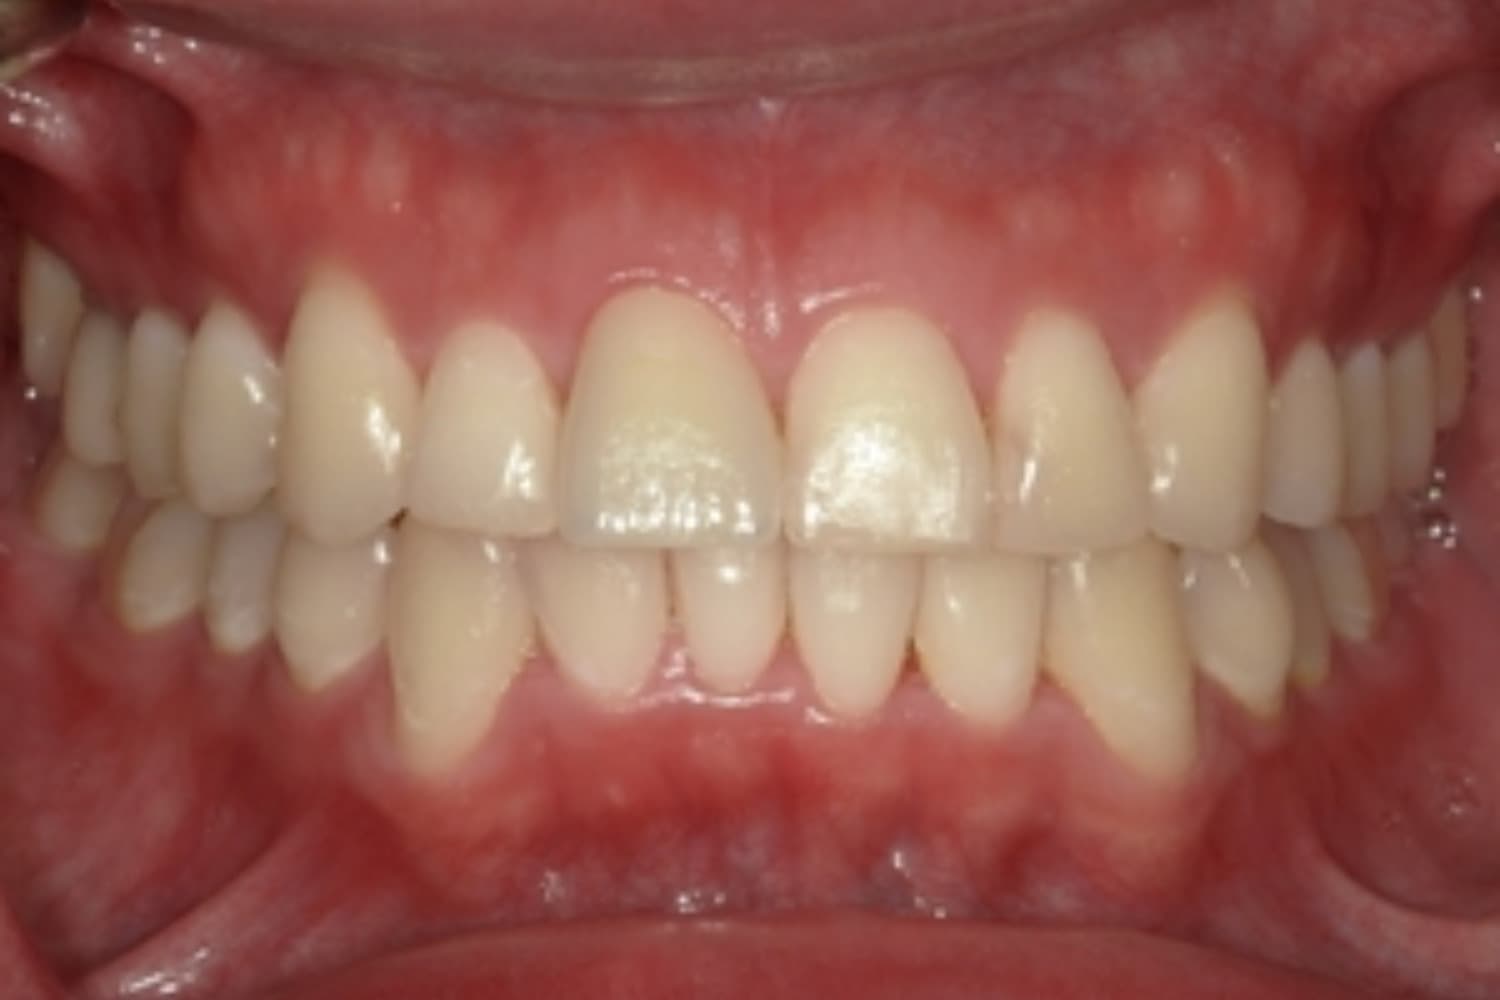

ガタガタとした歯並びや八重歯(1)

Before

After

ガタガタとした歯並びや八重歯をマウスピース矯正(インビザライン)にて治療

主訴

下の前歯のガタガタが気になる

治療期間

2年5カ月

費用

90万円

副作用・リスク

・矯正治療による歯の動きには個人差があり、想定より治療期間が延びることがあります。 ・矯正治療で歯を動かす際に痛みをともなうことがあります。 ・指示された通りに保定装置を装着しないと、歯並びや噛み合わせの後戻りを引き起こす可能性があります。